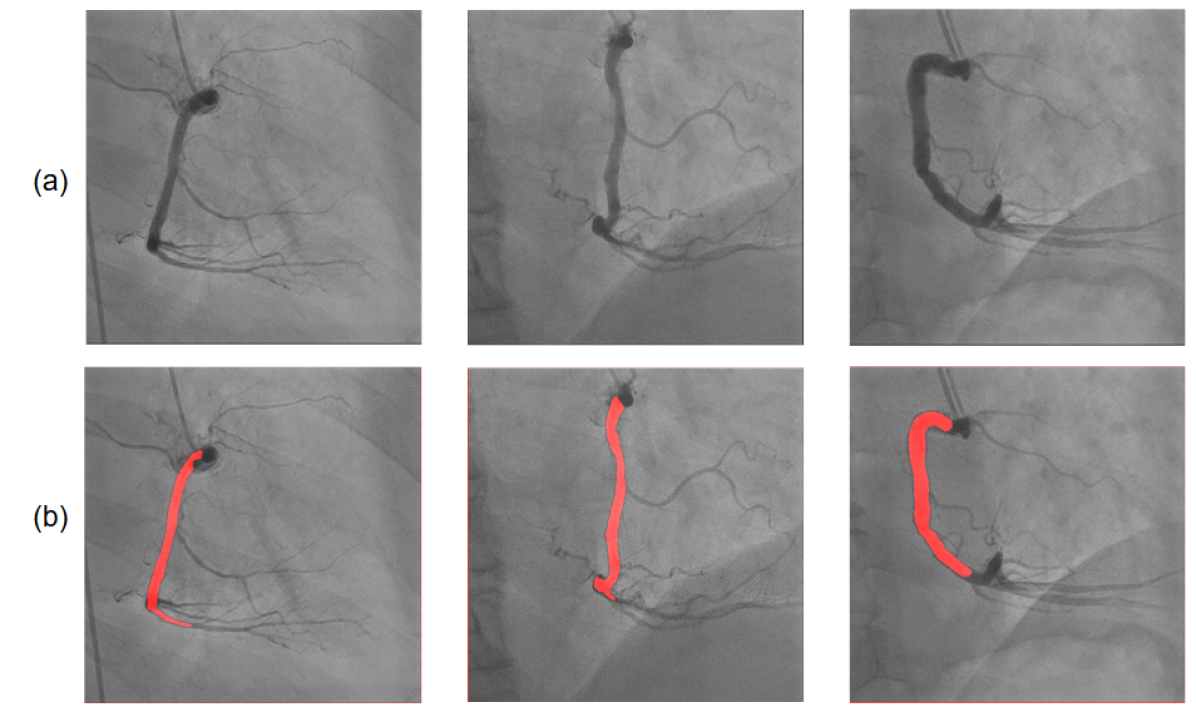

Figure 3: Illustration of LAO and RAO results. (A) Temporal score variation over the course of an LAO angiography video. Each data point represents the machine predicted score of that frame. Three particular frames are highlighted in red as they represent the frame just before, in and after the “key frame region”. (B) Machine’s inferential ability shown by noisy incorrect LAO labels detected by the model. First image: a key frame erroneously labeled as non-key in manual labeling, and the model gave the frame a high score (0.998) Second image: a non-key frame with vessel shifted out erroneously labeled as a key frame; it was detected and given a low score (0.083) (C) LAO vessel segmentation, (a) original images, (b) segmentation masks. (D) RAO vessel segmentation, (a) original images, (b) segmentation masks. (E) Erroneous LAO segmentation near the RCA bifurcation point. (F) Identification of LAO stenosis location and estimation of severity. (G) Side-by-side comparisons between LAO and RAO stenosis measurement. Each column represents one patient.

Key frame extraction and vessel segmentation performance evaluation on LAO and RAO data are presented in Table IV. A slight dip in performance is seen using the RAO view in comparison to LAO, which can be attributed to the fact that the models were intially trained on LAO data. However, results on RAO are remarkably robust, indicating that the trained models have some generalizability to vessels with similar anatomical structures. Segmentation F1-score for the RAO view also did not dip significantly. The predicted masks delineated the RCA vessel structures clearly and included appropriate endpoints at their distal bifurcations (Fig. 3D), which were landmarks learned from LAO labels. Further fine-tuning of the models on a moderate amount of true RAO labels can greatly boost performance if required.

As a preliminary exploration of how automated measurements of a given lesion from different views may be aggregated, we performed manual visual comparisons between the identified stenosis positions of lesions in LAO and RAO views (Fig. 3G). The algorithm could identify the correct location of the most severe blockage in nearly all videos (14/15 patients). The automatically boxed regions highlighting the most severe stenosis in the LAO and RAO views correspond to each other.